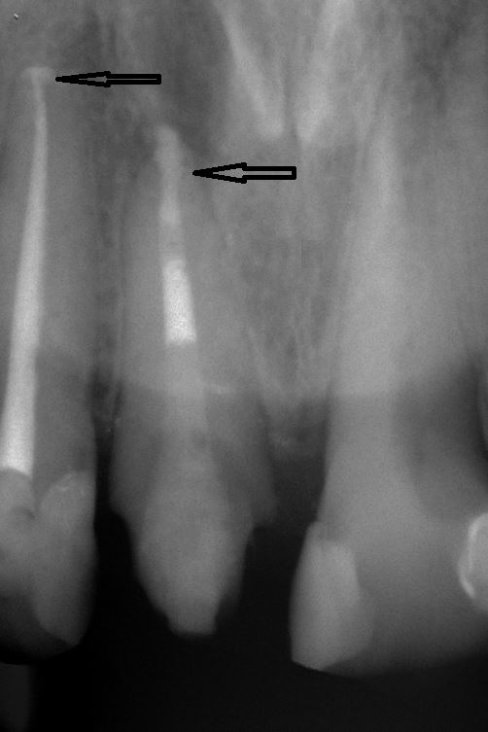

Fallbeispiel für eine unvollständige Wurzelfüllung

nach Revision und dichtem Verschluss